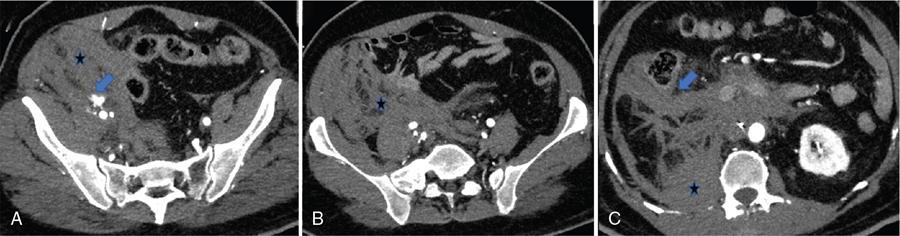

Image

Fig. 10.17.1.8 Contrast-enhanced axial (A–D) and sagittal CT (E) sections in a case of a pelvic retroperitoneal haematoma. The right kidney appears bulky with perinephric fat stranding. Active leak of contrast from the right external iliac artery is seen on the arterial phase (blue arrow in A) with a resultant large haematoma (asterisks in A–D). Superiorly, it extends along the combined interfascial plane into the perirenal space (blue arrow in E) as well as along the retromesenteric (blue arrows in C and D) and retrorenal planes (asterisk in C). Medially the haematoma tracks into the central compartment (asterisk in D) via the perirenal space.